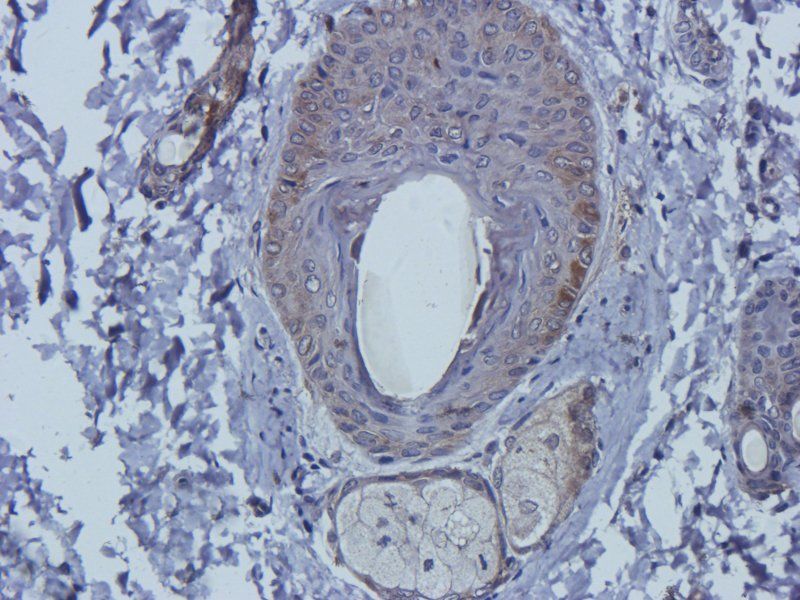

应用稀释比例:WB: 1:200-2000, IHC-P: 1:100-500, IF/ICC: 1:100-500

KLH conjugated synthetic peptide derived from human Mlkl. Please contact us for the exact immunogen sequence. The peptide is available as orb374793.

别名:anti-Mixed lineage kinase domain-like protein antibody, anti-Mlkl antibody